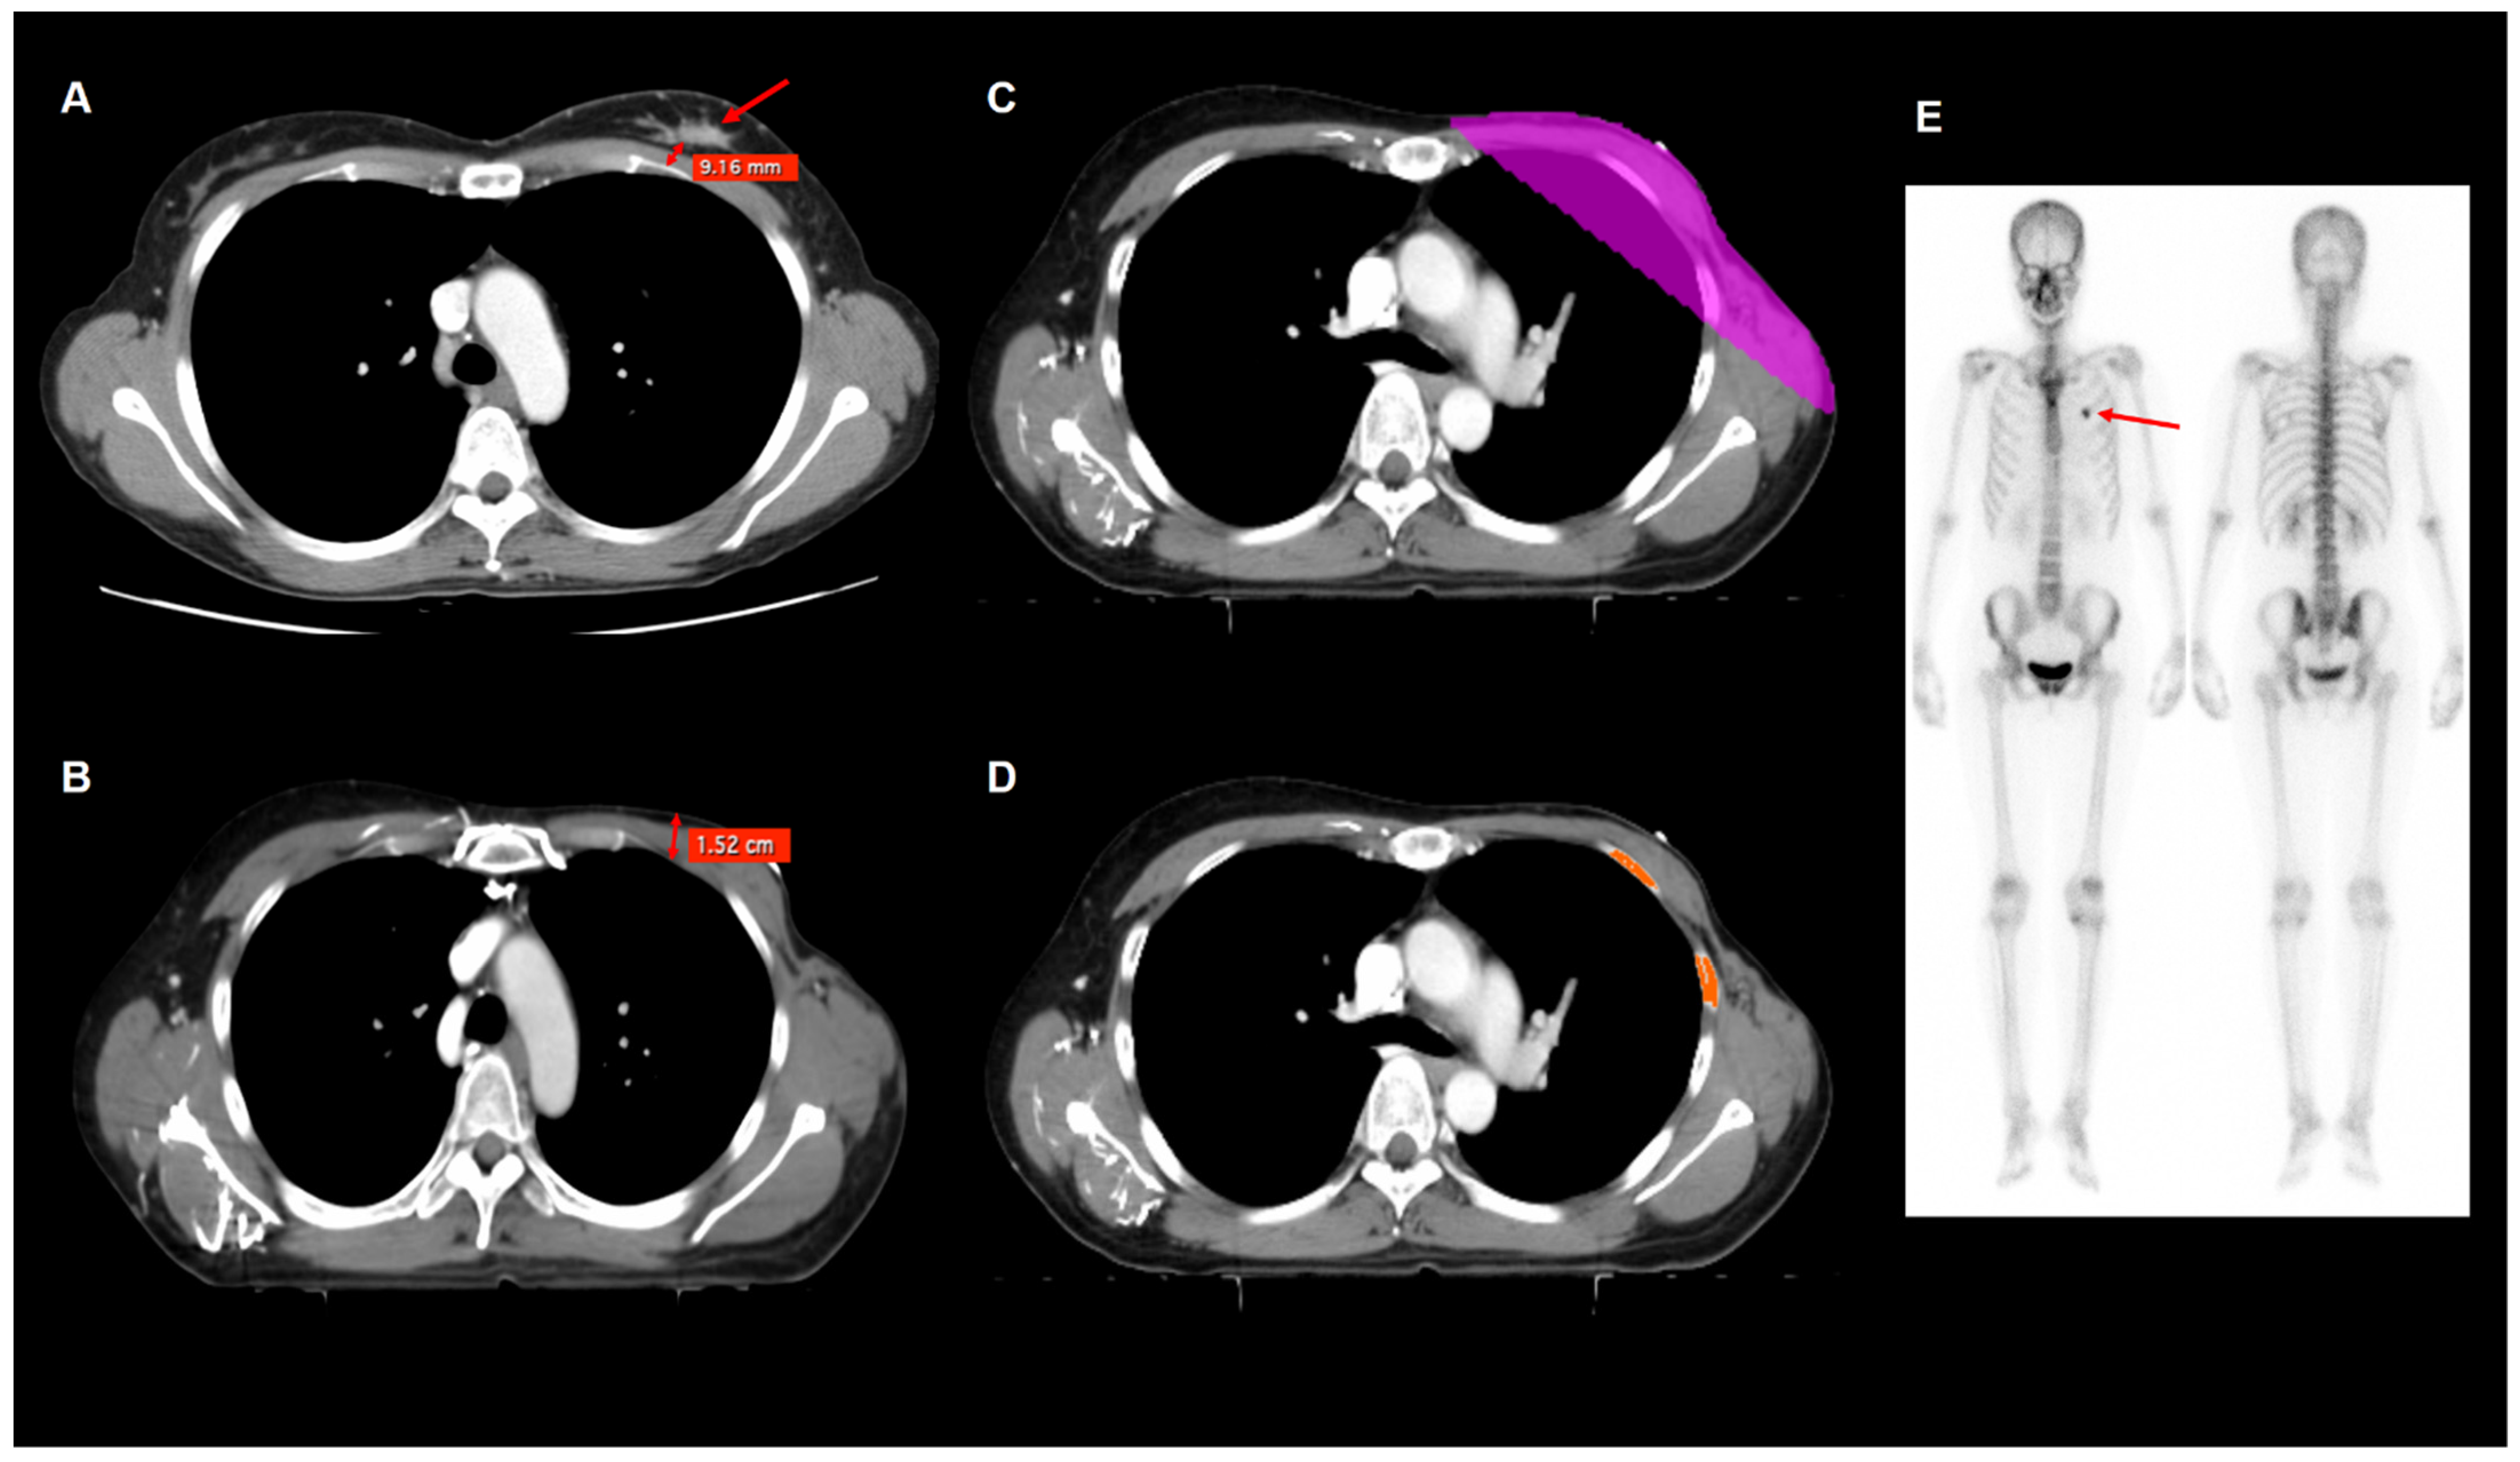

2.4. Imaging Analysis